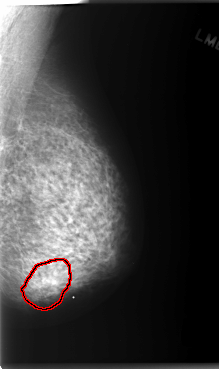

C_0148_1.LEFT_MLO

FILE: C_0148_1.LEFT_MLO.OVERLAY

TOTAL_ABNORMALITIES 1

ABNORMALITY 1

LESION_TYPE MASS SHAPE LOBULATED MARGINS ILL_DEFINED

ASSESSMENT 4

SUBTLETY 1

PATHOLOGY MALIGNANT

TOTAL_OUTLINES 1

BOUNDARY